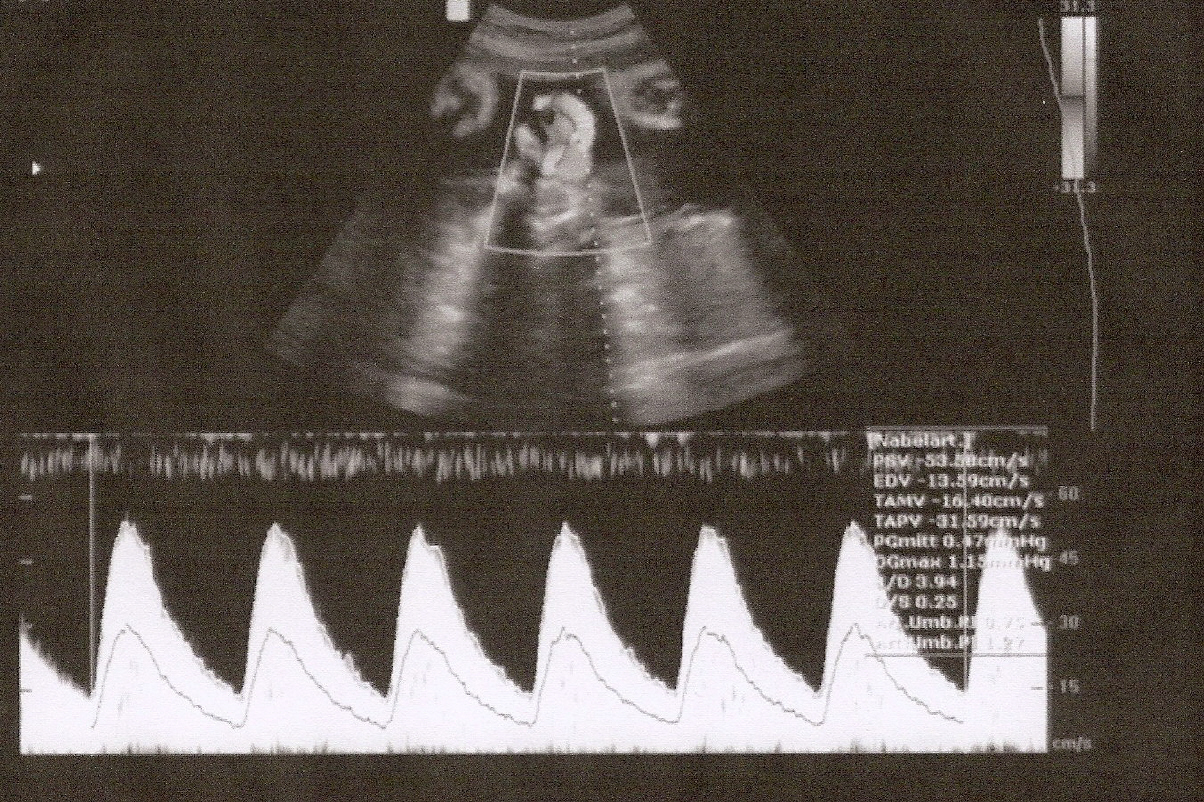

Mit Dopplersonografie bezeichnet man eine spezielle Ultraschalluntersuchung von Gefäßen; dabei werden Blutflüße in bestimmten Gefäßen gemessen. In der Geburtshilfe sind dabei bestimmte fetale (=kindliche) sowie maternale (=mütterliche) Gefäße relevant, die v.a. eine Aussage über die Versorgung des Kindes erlauben. Da Auffälligkeiten der Blutflußkurven in der Regel deutlich früher auftreten als CTG-veränderungen, können Mangelversorgungen des Kindes mittels Dopplersonografie früher erkannt werden.

Die Dopplersonografie läßt somit frühzeitig fetale Gefährdungssituationen erkennen, in denen sowohl eine intensivere vorgeburtliche Betreuung als auch in Einzelfällen eine vorzeitige Entbindung notwendig werden kann. Daher sollte in bestimmten Situationen, wie z.B. erhöhtem Blutdruck der Schwangeren, vorausgegangener Schwangerschaft mit Gestose oder Mangelgeburt, die Schwangerschaft zusätzlich mit dopplersonografischen Untersuchungen überwacht werden.

Andererseits kann mittels Dopplersonografie zur Abklärung von CTG-auffälligkeiten, bei Wachstumsrückstand des Feten und/oder verminderte Fruchtwassermenge eine Mangelversorgungssituation ausgeschlossen werden.